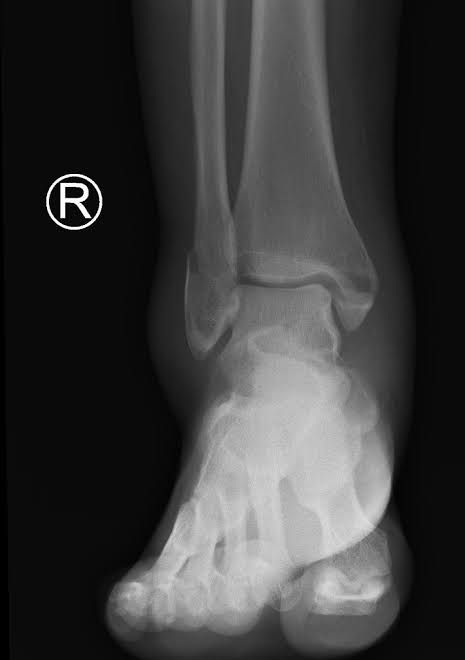

A "bimalleolar equivalent" fracture means that in addition to one of the malleoli being fractured, the ligaments on the inside (medial) side of the ankle are injured. Usually, this means that the fibula is broken along with injury to the medial ligaments, making the ankle unstable.